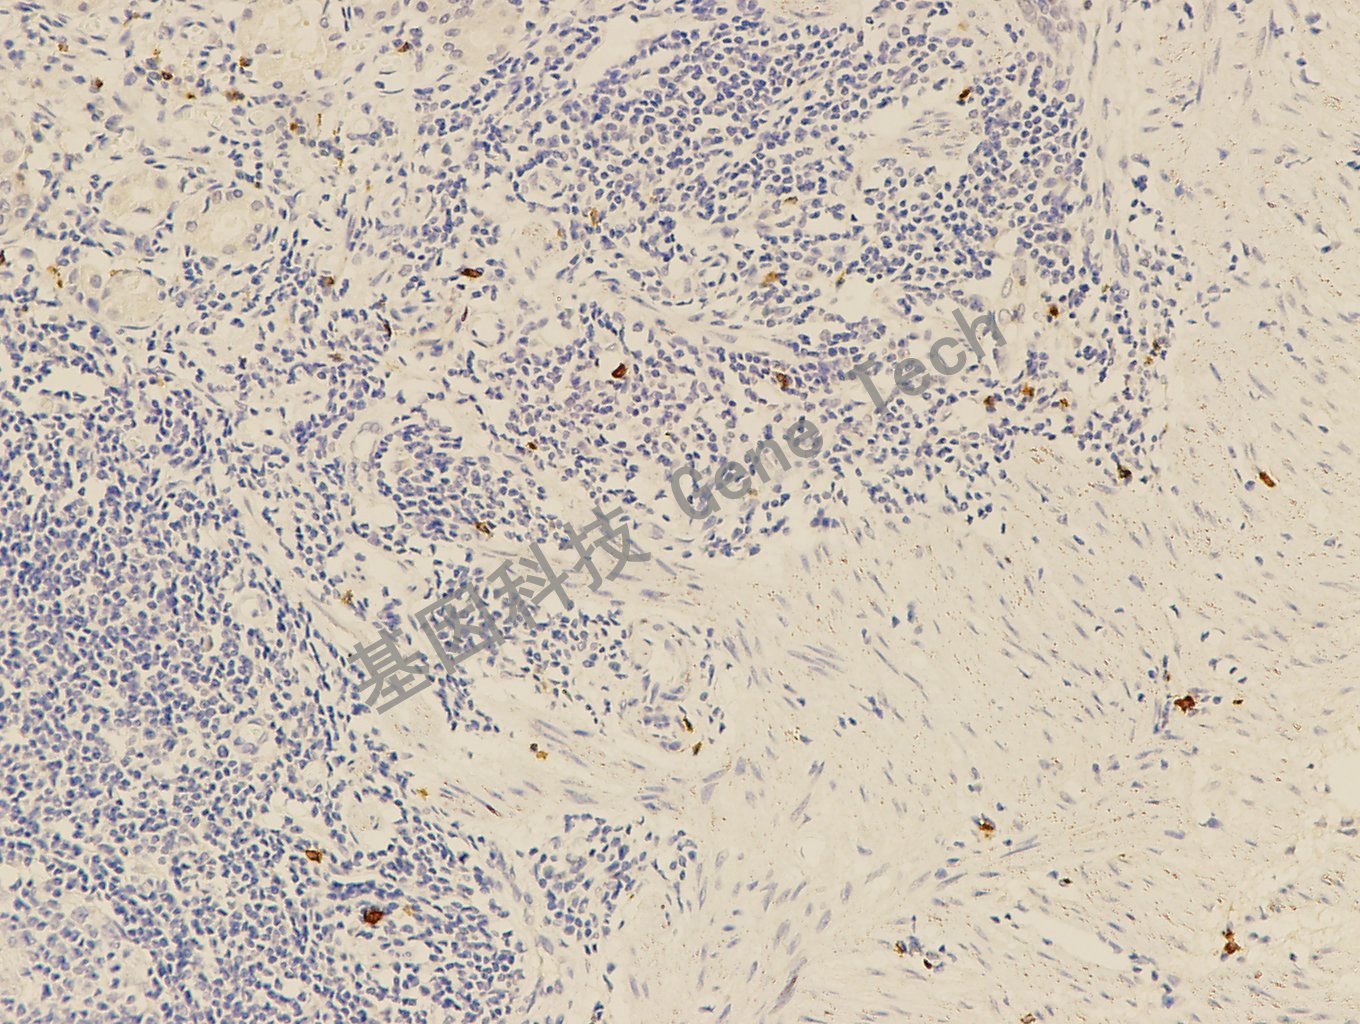

扁桃体石蜡切片,用 Granzyme B(GT2297)染色,细胞浆阳性,DAB 显色。